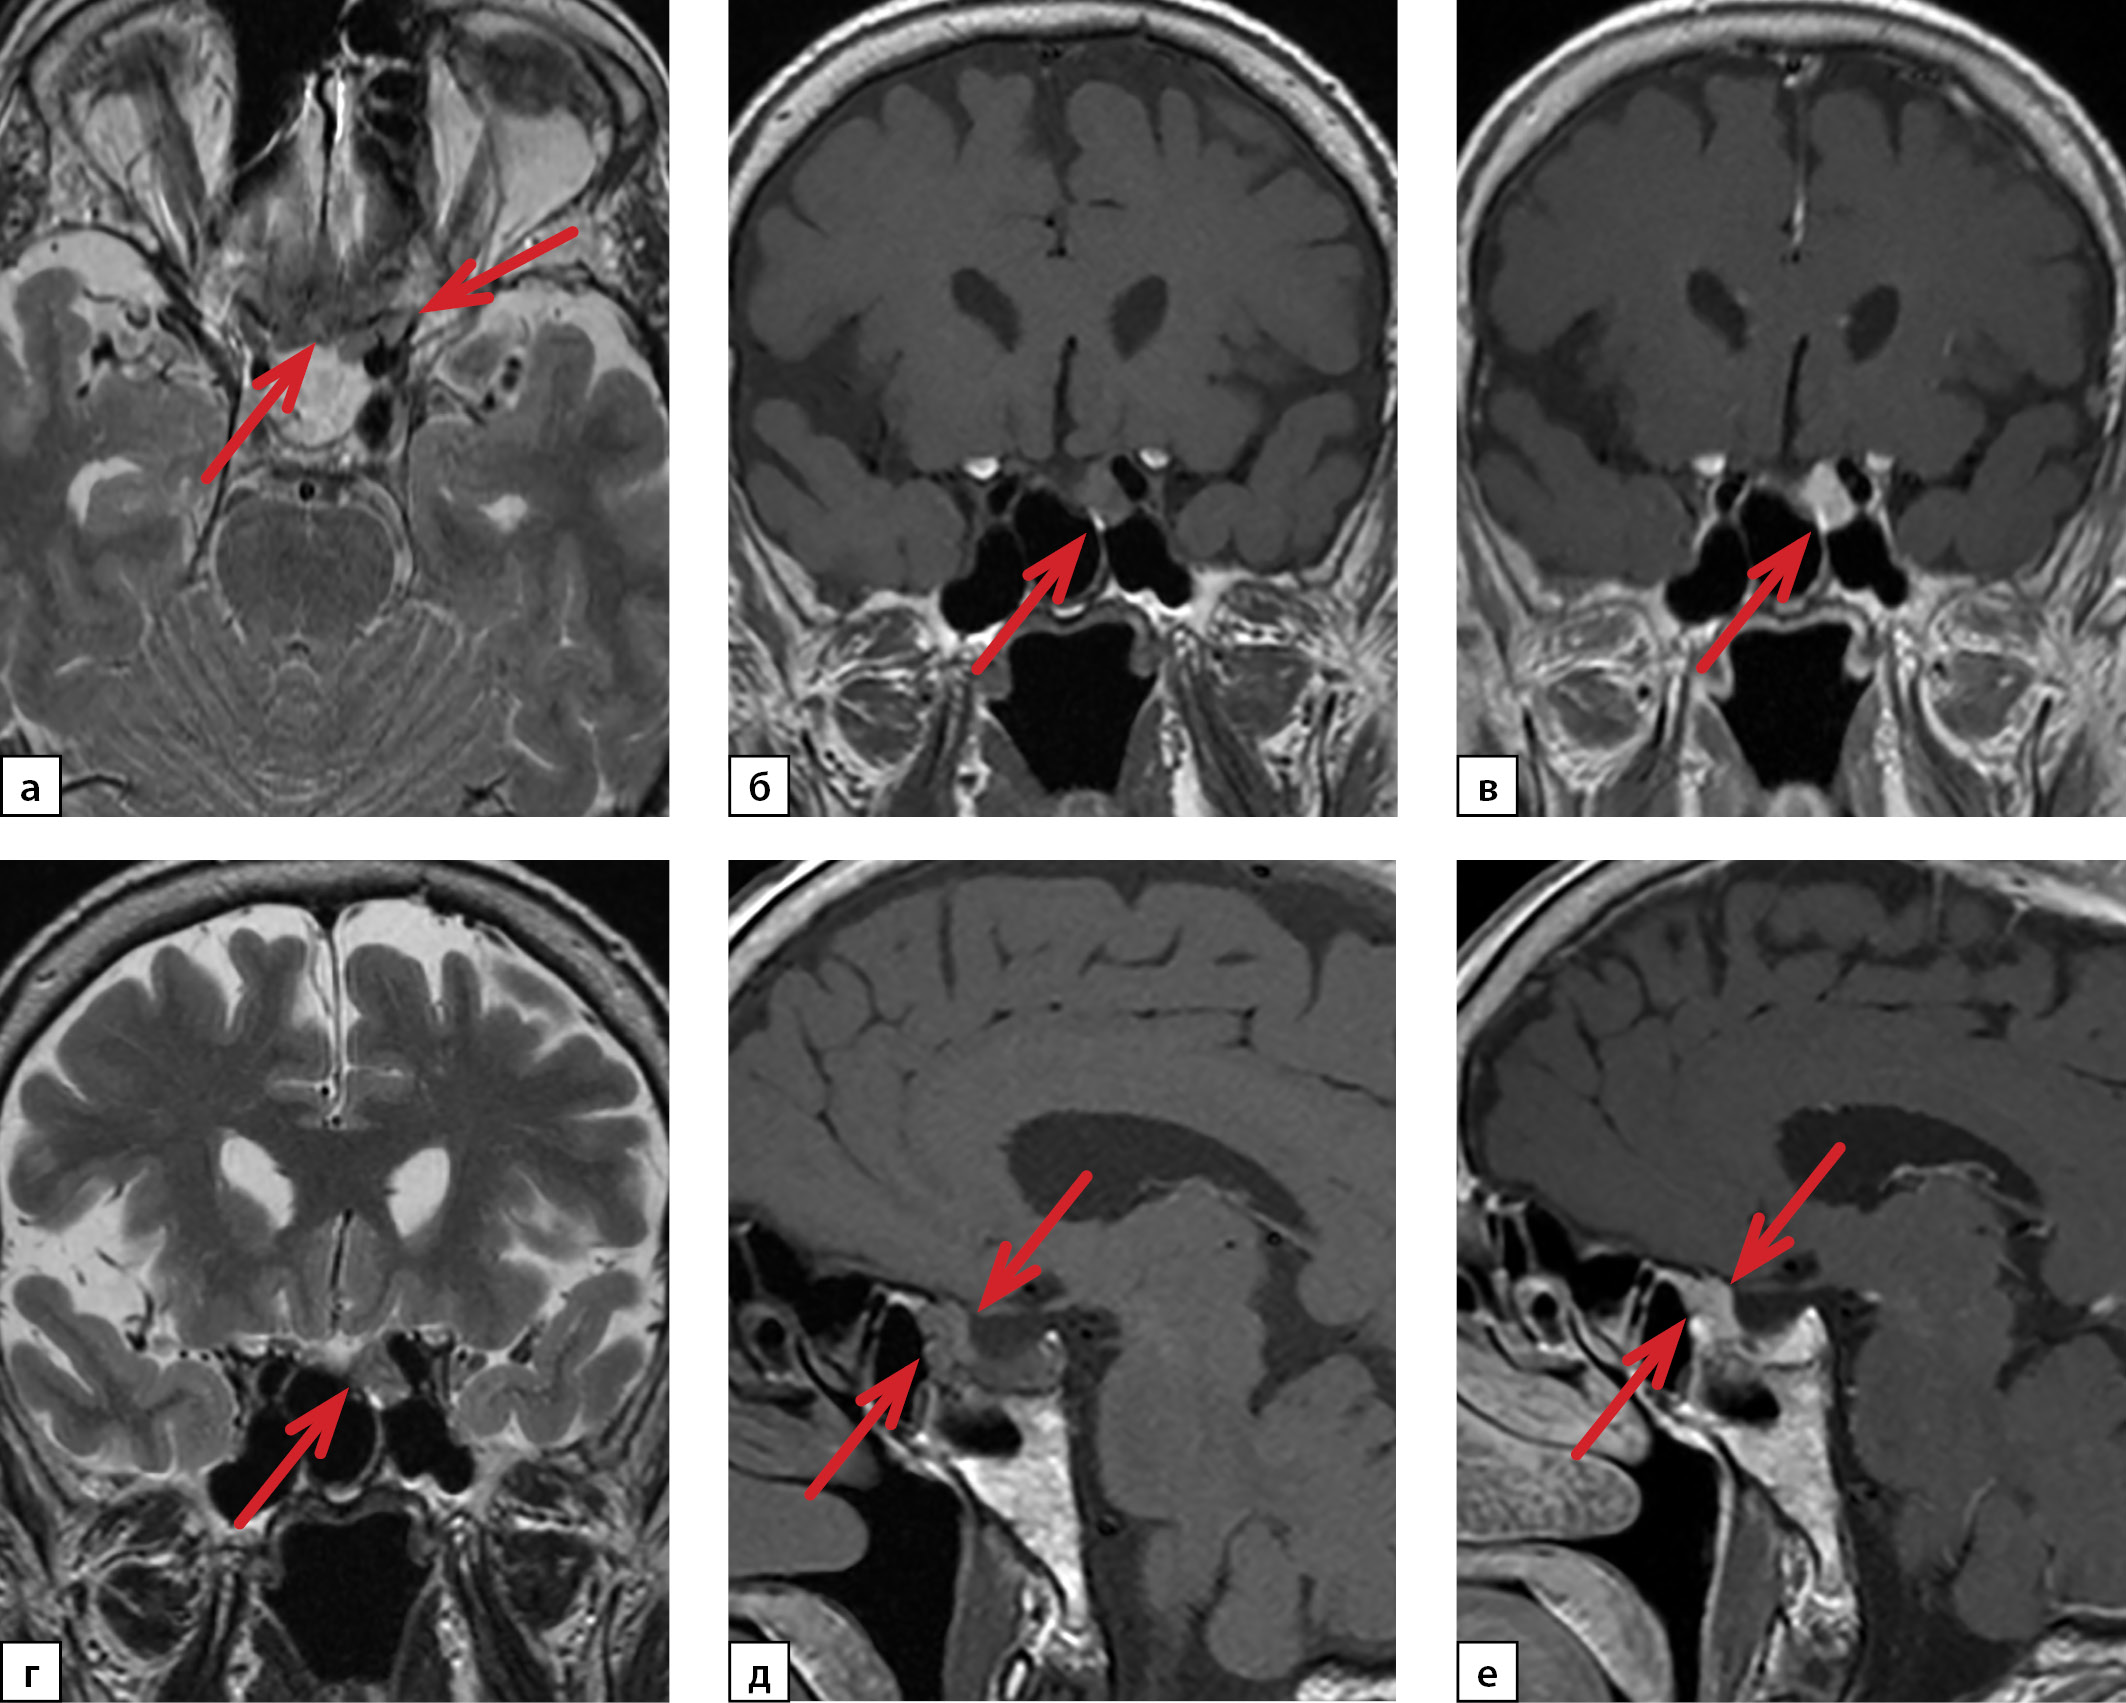

В результате проведения КТ брюшной полости и забрюшинного пространства с контрастированием (рис. 2) в левом надпочечнике визуализировано округлое образование размерами 30×33 мм, плотностью +16–(+)30 HU, с ровными и четкими контурами, неравномерно накапливающее контрастный препарат (в портальную фазу контрастирования до +83 HU, в отсроченную фазу — без значимого вымывания контрастного препарата; в структуре определены участки, не накапливающие контрастный препарат).

Рисунок 2. Компьютерная томография

органов брюшной полости с контрастированием:

а — нативное сканирование;

б — артериальная фаза;

в, г — венозная фаза;

д — отсроченная фаза.

Редкость смешанной гормональной продукции одной опухолью представляет трудность в дифференциальной диагностике подобных случаев с наличием сочетанной патологии с гиперсекрецией гормонов из разных источников. В представленном клиническом случае наличие смешанной артериальной гипертензии с пароксизмальными приступами повышения уровня АД, сопровождающейся ощущением дрожи в теле, тремором рук, выраженной общей слабостью, повышенной потливостью, чувством страха, в сочетании с выявленными повышенными уровнями метанефрина и норметанефрина плазмы свидетельствовали в пользу катехоламин-продуцирующей опухоли. Обращал на себя внимание факт незначительного повышения уровня метанефрина при превышении уровня норметанефрина более чем на 20 норм, что не позволяло исключить наличие ПГ. При КТ визуализировано новообразование надпочечника высокой плотности, однако распределение контрастного вещества с низким накоплением в артериальную фазу, максимальным накоплением в венозную фазу и слабым выведением в отсроченную фазу, что более характерно для адренокортикальных карцином, чем для ФЕО [10–12].